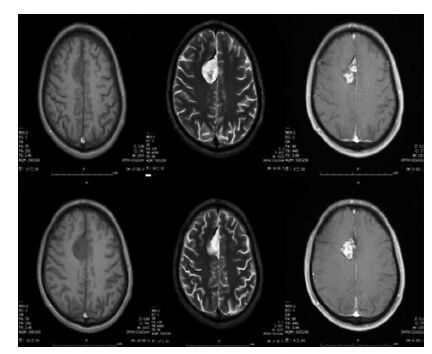

这些肿瘤在MRI T2加权像上表现为高信号。1/2的病例存在囊肿,约1/3的病例存在钙化。对比增强程度不一,可能无强化,也可能明显强化,可能是病灶实体或边缘强化。

MRI特征与其他神经元-胶质肿瘤类似。大多数病变有囊性成分和可强化的实性成分,其T2加权像表现为等信号高信号。也可能观察到钙化。在大多数病例中,乳头状胶质神经元肿瘤可通过外科切除治愈。少见的复发性或进行性乳头状胶质神经元肿瘤也有报道,通常与Ki-67指数升高有关(>5%)。